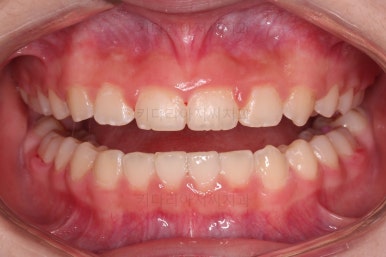

초진 시 입안의 모습입니다.

앞니가 안으로 굽어 들어간 양상인데요. 흔히 "옥니"라고 표현합니다.(뻐드렁니의 반대개념)

전반적으로 치열이 삐뚤삐뚤하고요.

오른쪽 상단 사진을 보시면 어금니의 높이와 앞니의 높이가 차이가 많이 납니다.

앞니가 솟구쳐 있는 양상인데요.

그 이유 때문에 어금니로 다물었을 때의 위아래 앞니가 많이 겹쳐서 아래 앞니가 아예 보이지 않는 상황이었어요.

이를 "과개교합"이라고 표현합니다.

그리고 전반적으로 아래 치열이 윗니에 비해 뒤로 밀려 있어서, 어금니의 맞물림이 좋지 못하고 듬성듬성해 보이는 상황이었어요.